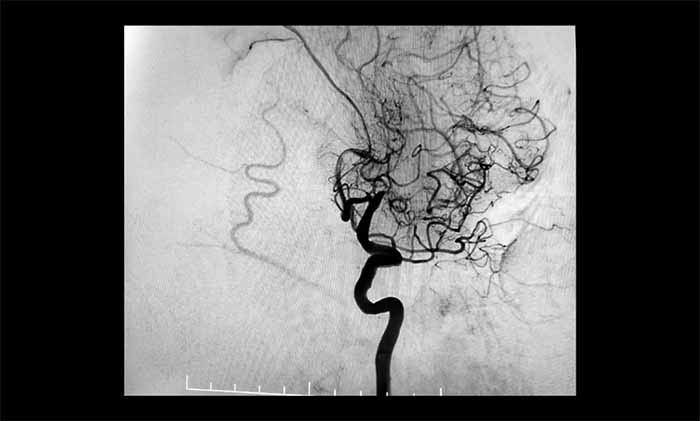

近日,一位70多岁患者因反复出现右侧肢体无力、言语含糊、口角流涎,被诊断为左侧大脑中动脉完全闭塞。他还合并颈内动脉动脉瘤、椎动脉狭窄等复杂问题,手术难度极高。其中,左侧大脑中动脉M1段的慢性完全性闭塞,是导致其神经功能缺损反复加重的主要原因。

席刚明教授、王贵平博士团队经过全面评估,最终在全麻下精细操作,利用微导丝穿过闭塞段,并以“球囊扩张+支架置入”完成血管再通,为患者打通这条关键的“生命线”。术后患者血流通畅,恢复良好。

▲ 左侧大脑中动脉完全闭塞

▲ 左侧大脑中动脉顺利开通